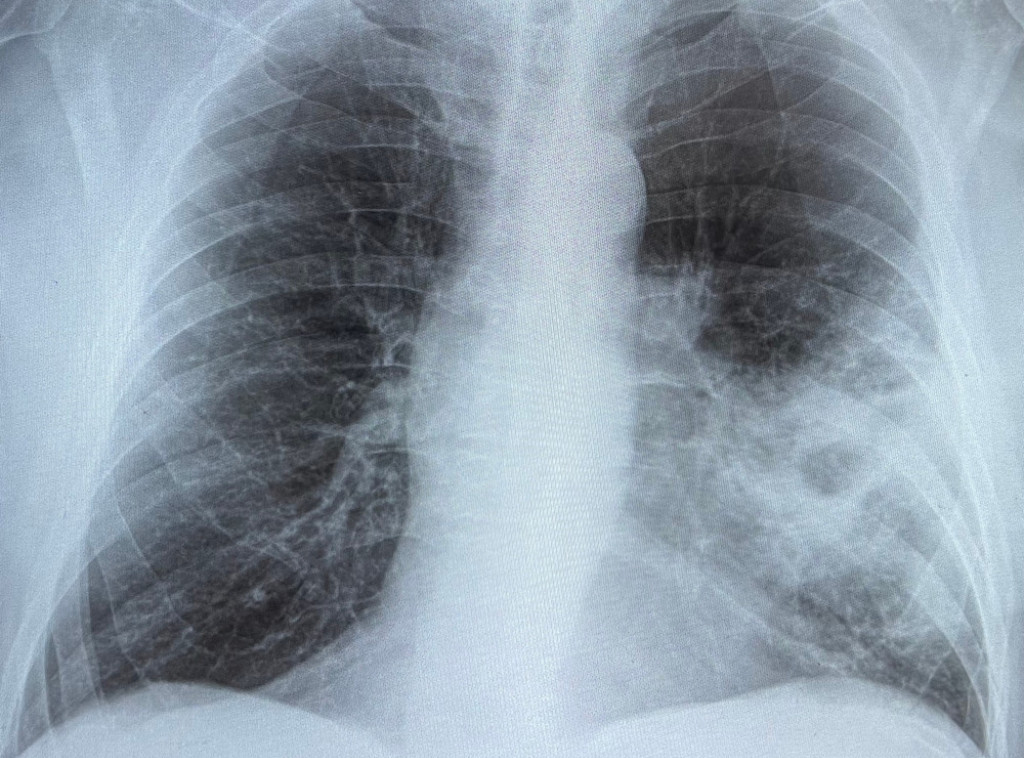

Brazil: Bolsonaro u bolnici zbog upale pluća, stabilan na intenzivnoj nezi

Više od pola miliona slučajeva upale pluća zahtevalo hitnu bolničku pomoć u Engleskoj

Vatikan: Papi Franji dijagnostikovana obostrana početna upala pluća

Papa Franja ima upalu pluća